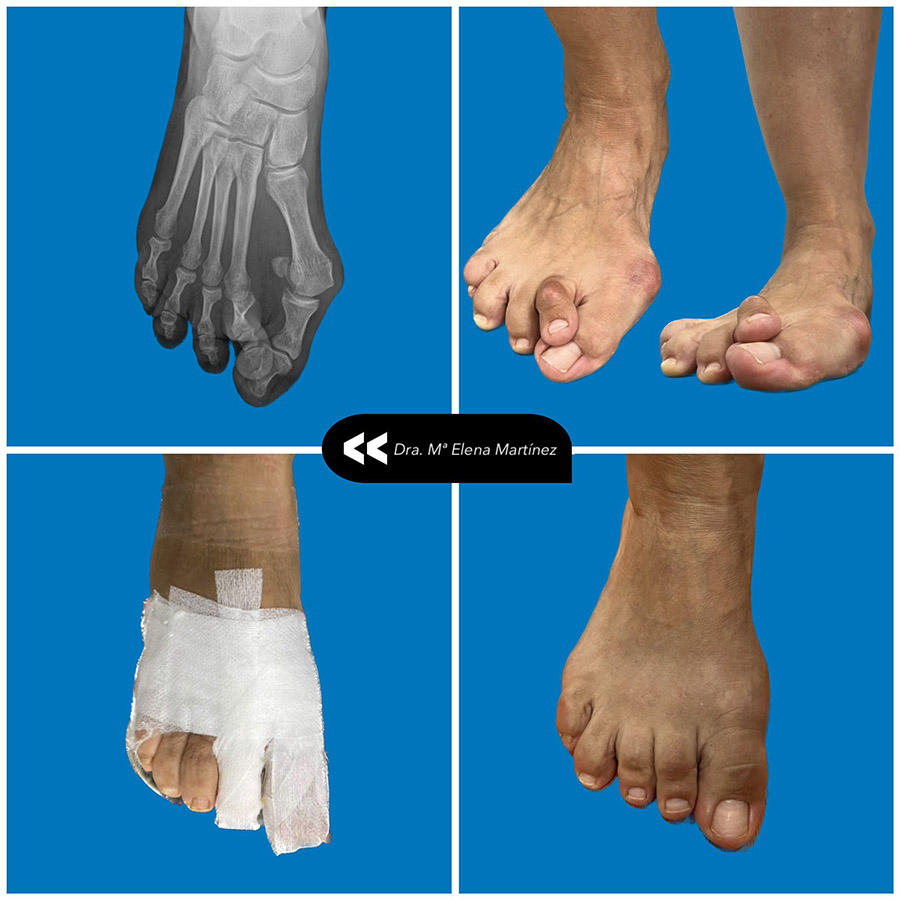

Dra. Mª Elena Martínez Mendoza

La Dra. Elena forma parte del equipo quirúrgico de Hermez Centro Médico y está especialmente dedicada a la biomecánica, la podología deportiva y la cirugía del pie.

• Máster en Cirugía Podológica de Mínima Incisión

Su enfoque combina precisión técnica, visión funcional y recuperación progresiva del paciente.